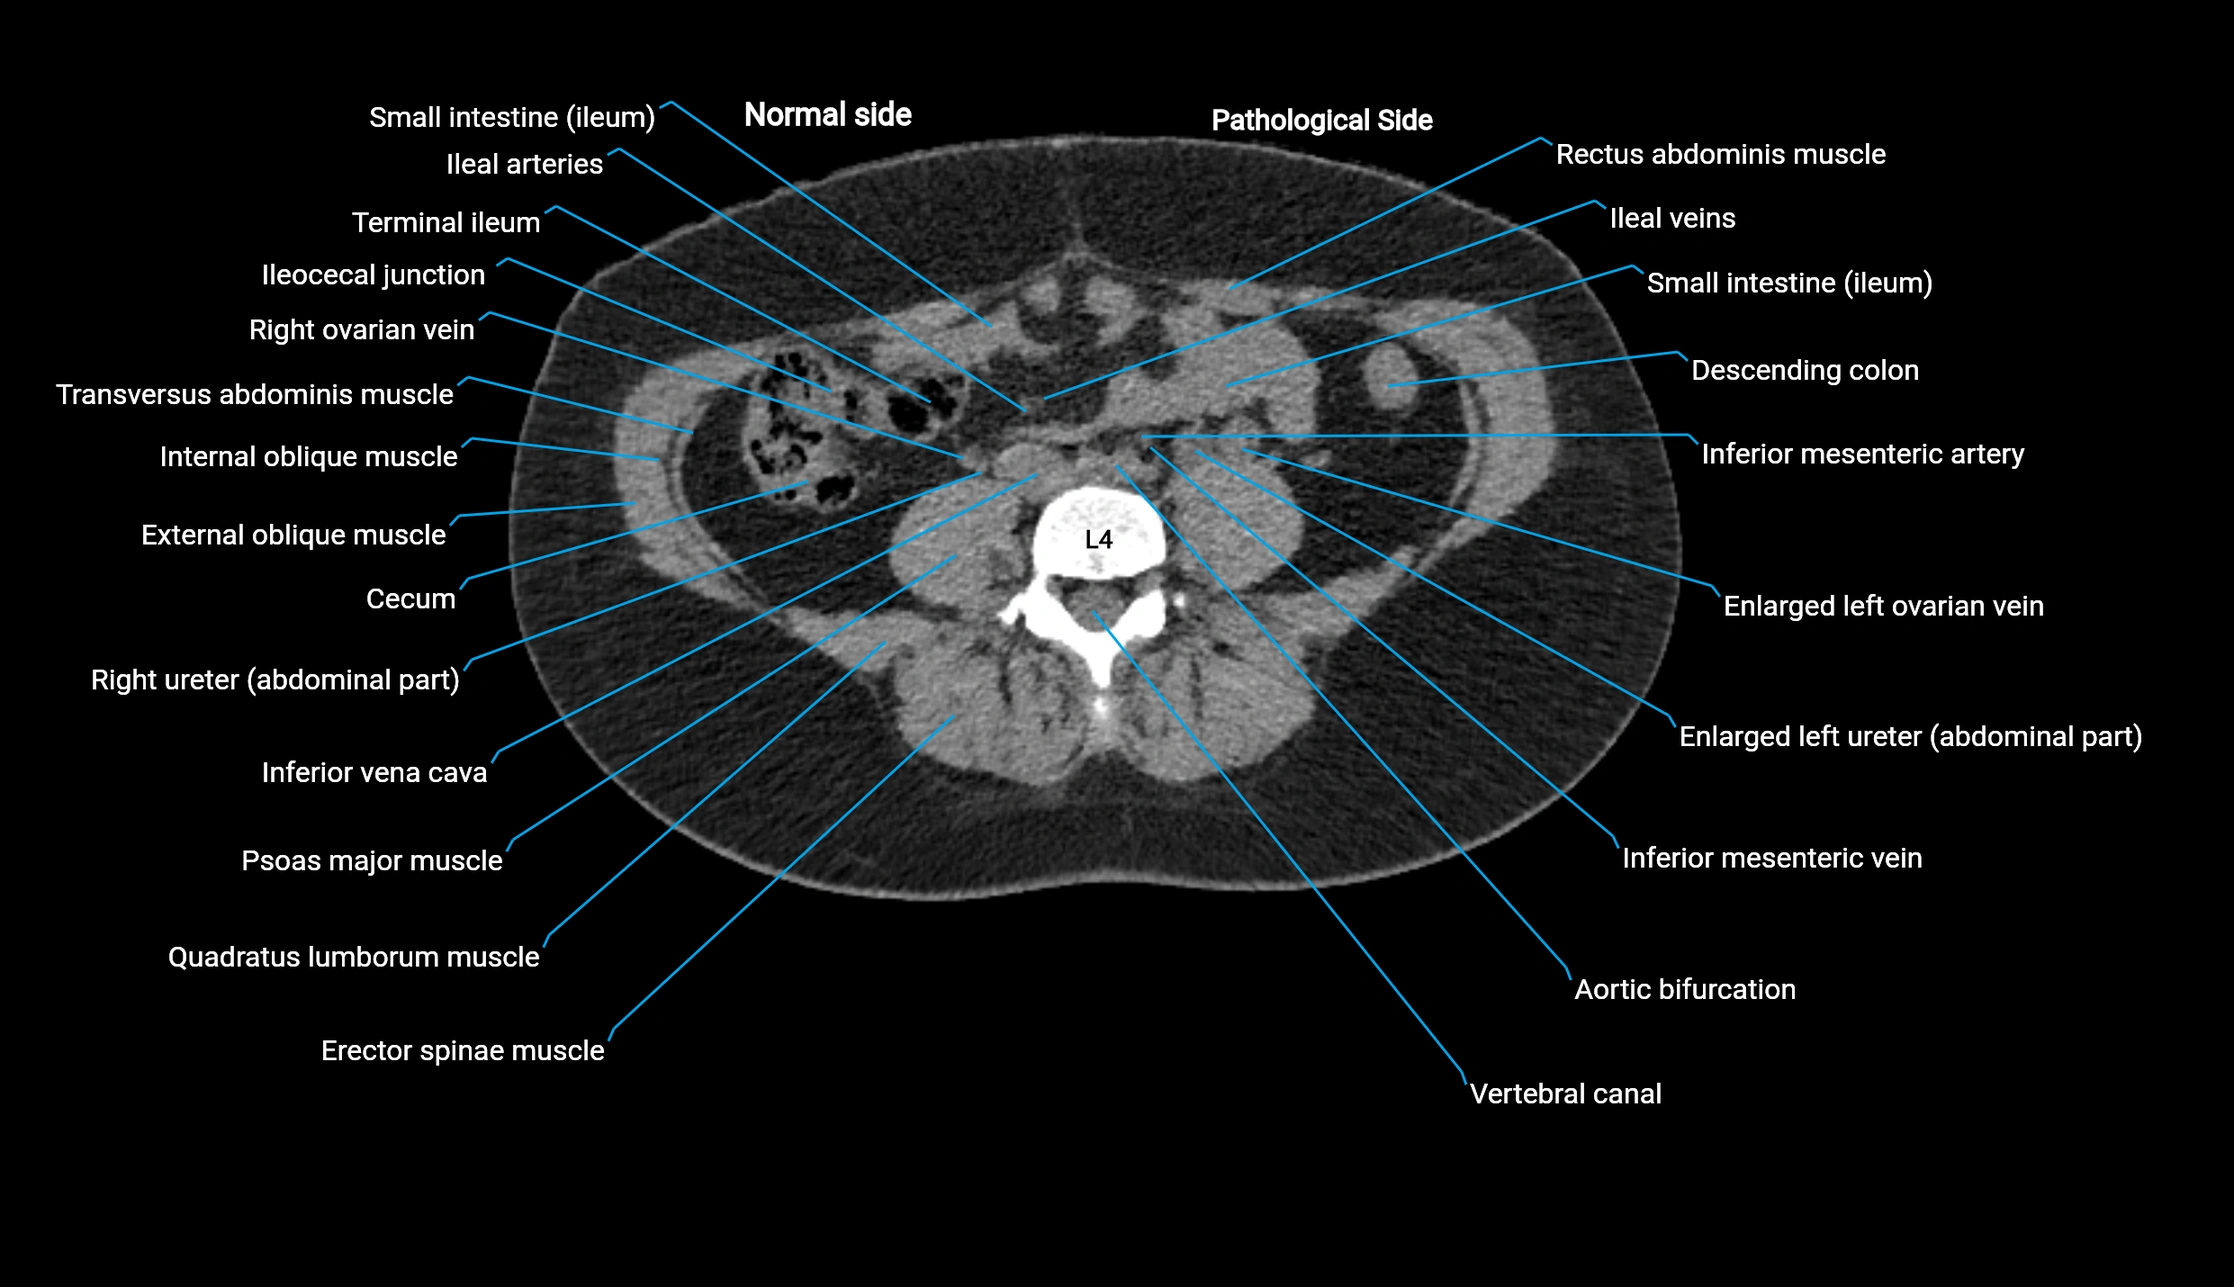

CT image

image